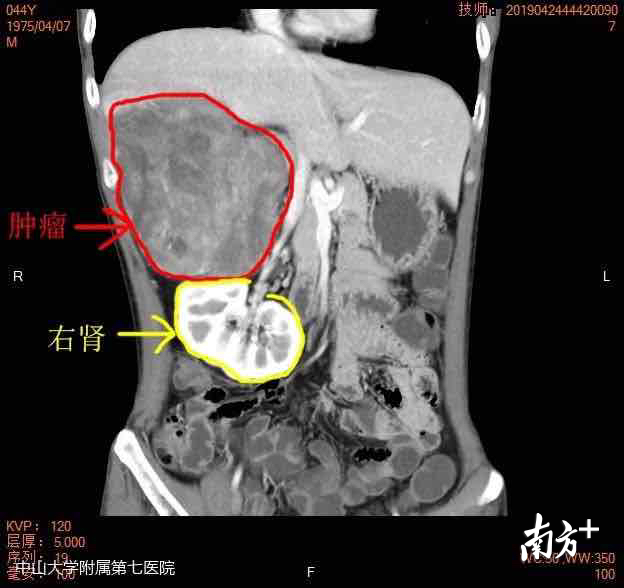

广东44岁的林先生(化名)右腹部长了一个巨大的腹膜后肿瘤,有橄榄球大小,不仅包绕着右肾动静脉,还累及周边多个组织器官、血管和神经,将右腹腔的脏器都挤压到了左侧,脱离了正常的生理部位,导致右肾面临自体移植的风险。

林先生今年44岁,4月份起逐渐感觉右侧腹部点闷胀,躺着的时候目测右边肚子比左边的肚子稍高。在粤东当地医院做了腹部CT,竟然发现肚子里长了一个大肿物。到广州的大医院作进一步检查治疗。在广州,林先生做了PET-CT,发现肿物已长大,病理诊断为去分化脂肪肉瘤。

去分化脂肪肉瘤是一种高度恶性的肿瘤,手术是主要治疗手段。不过,林先生的情况又非常特殊。“体内的肿物呈马蹄形,累及了周边多个组织器官,包绕了重要血管,而且肿瘤周边血供非常丰富,稍有不慎很可能危及生命。”中山大学附属第七医院院长何裕隆说。

手术最难的就是要分离重要血管,“救”右肾。“患者的肿瘤非常大,相比在广州时做的检查,已经长大了近一倍,有橄榄球那么大。而且肿瘤还包绕着右肾动静脉,将右肾下压脱离了正常的生理部位,手术中可能需要做右肾分离和自体移植。”何裕隆说。同时,肿瘤还贴近下腔静脉,并有部分侵及。

此外,肿瘤已累及周边组织器官和神经,上方侵及部分右侧膈肌,后方侵及腰大肌、腰方肌,与胸、腰神经干关系密切,手术很容易伤及神经,导致感觉、运动功能障碍等后遗症。